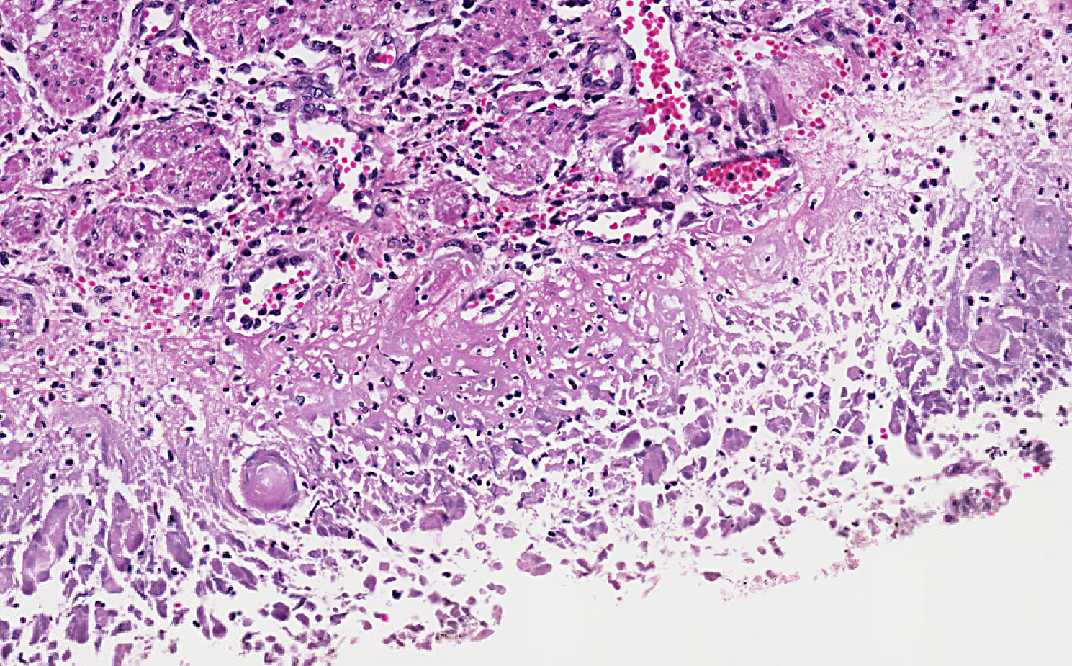

Area 2: The features are similar to that of Area 1 except that the 3M cells are more easily seen.

• At the edge of both ulcers, there are multinucleated cells. These nuclei are the so called 3M nuclei which stands for molding of nuclei, margination of chromatin, and multinucleated. It is important to note that these nuclei are typically found at the edge of the biopsy specimen. If the endoscopist has biopsied only the center of the ulcer, it may be difficult to establish the diagnosis based on histopathology alone.